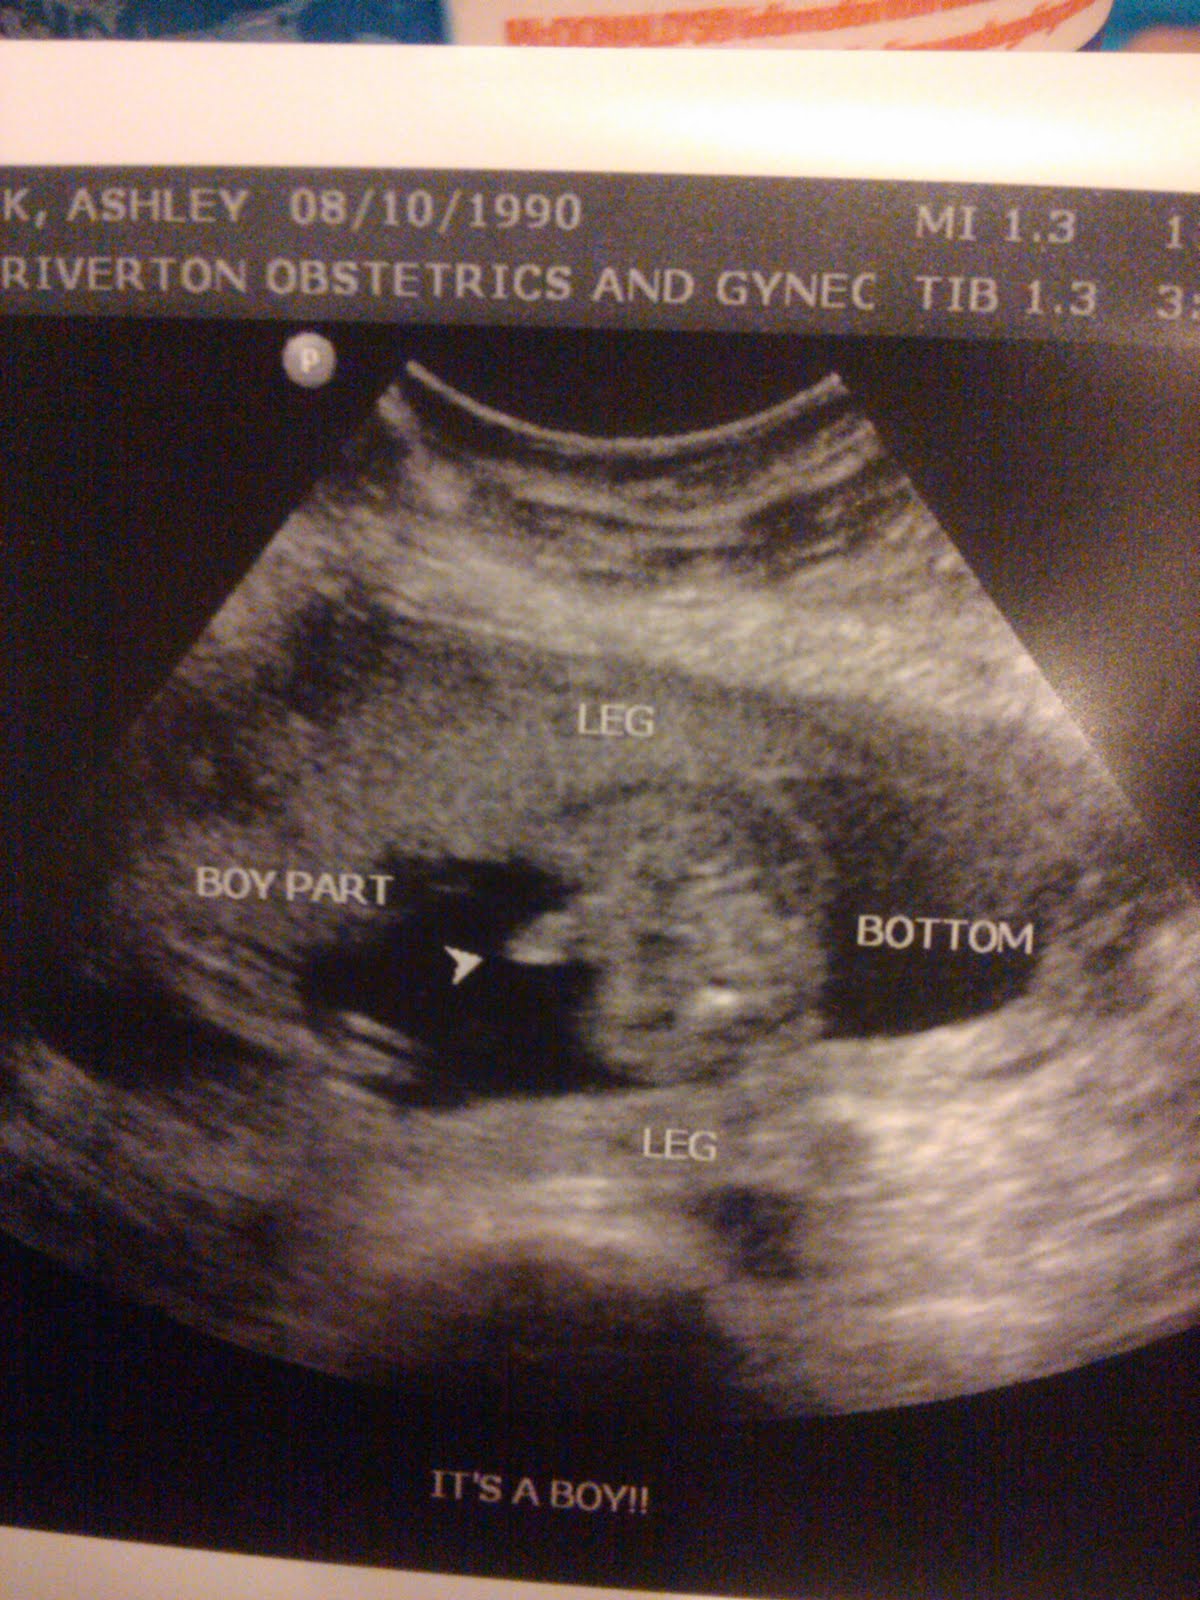

IT'S A BOY!! Yup! That's right, I'm gonna have a son come this April. Yikes, that's scary.

| Profile of William and his "button nose" maybe he'll have button eyes as well O.O |